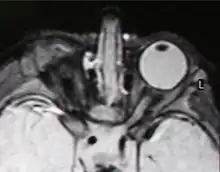

| Right-sided anophthalmia (MR image) | |

MRI/CT

MRIs and CTs can be used to scan the brain and orbits. Radiologists use this to assess the internal structures of the globe, the optic nerve and extraocular muscles, and brain anatomy.